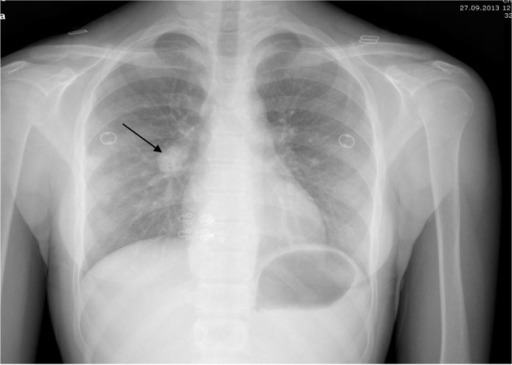

What's the Diagnosis?

Guess 1 / 5